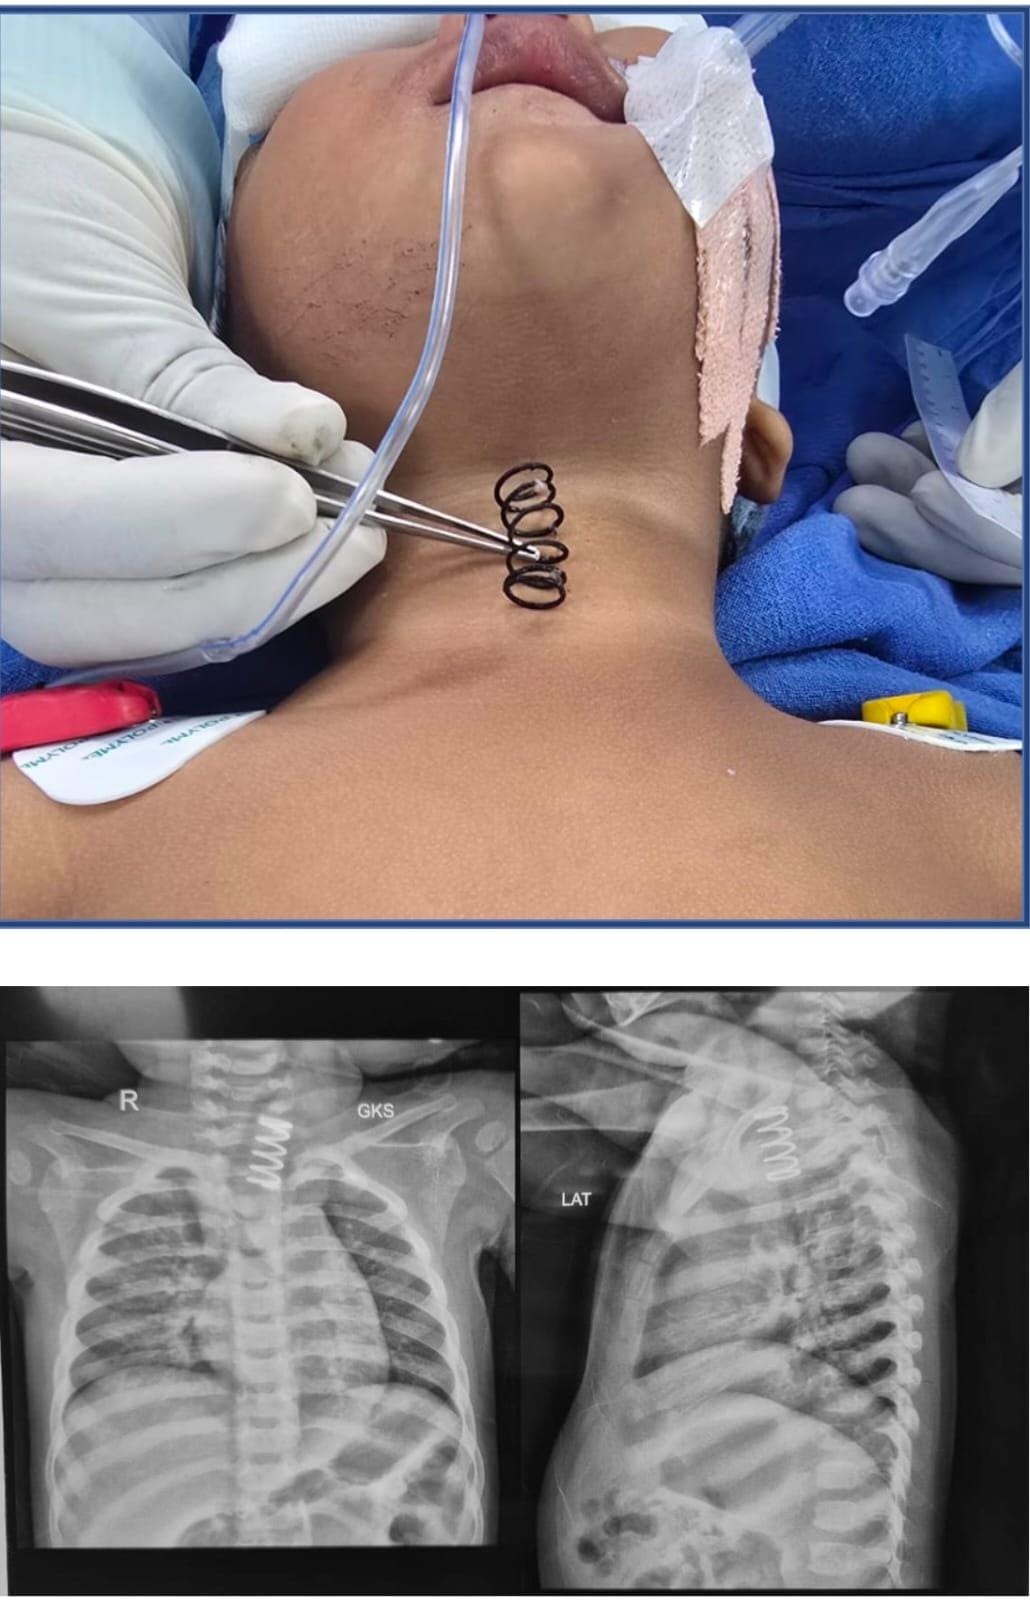

The metal spring stuck in the oesophagus, also known as the food pipe, was successfully removed after an endoscopic surgery, AIIMS said in an official statement.

“The spring was stuck on the upper part of the food pipe. And the thickness of the spring was much more than the normal spring, which we see in our pens. It was approximately half an inch wide and at least 1.5 to 2 inches long,” Professor Dr. Vishesh Jain, from the Paediatric Surgery Department, told AHN.

Jain and his team used advanced endoscopic techniques in the operating room. The spring was carefully rotated and removed, preventing any perforation, the statement said.